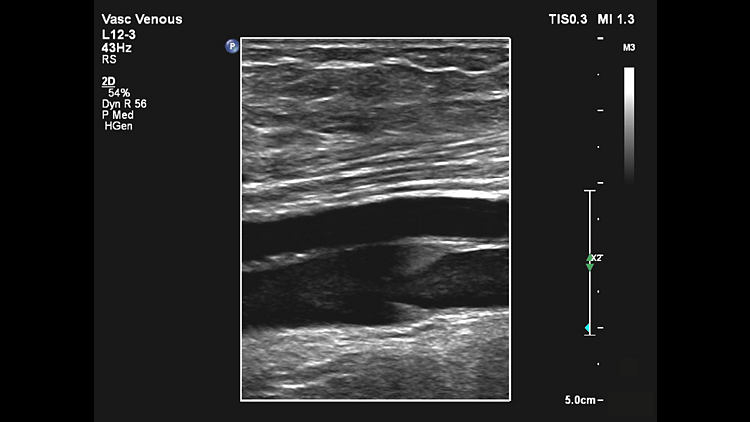

L12-3